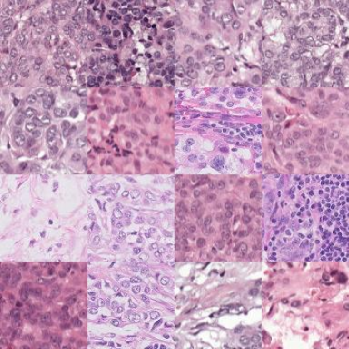

The first setting that we consider is histopathology. Different staining procedures followed by different hospitals lead to distribution shifts that can challenge a machine learning model that has only encountered images from a particular hospital. The CAMELYON17 challenge by Bandi et al. (2018) aims to improve generalization capabilities of automated solutions and reduce the workload on pathologists that have to manually label those cases. The corresponding dataset contains whole-slide images from five different hospitals and the task is to predict whether the histological lymph node sections captured by the images contain cancerous cells, indicating breast cancer metastases. Two of the hospital datasets provided by the challenge are held-out for out-of-distribution evaluation and three are considered in-distribution, because they use similar staining procedures. We consider this as the simplest setting for our experiments, because there are no extreme prevalence or demographic shifts. Additionally, the considered image resolution (96×96969696\times 96) is smaller in comparison to the imaging modalities presented later, which allows generation directly at that resolution without requiring an upsampler. The labelled dataset contains 455,954455954455,954 images, while the unlabelled dataset contains 1.81.81.8 million images from the three training hospitals; full statistics are given in Table A1. The unlabelled dataset does contain the hospital identifier, but not the diagnostic label.

In order to understand the impact of the number of labelled examples on fairness and overall performance, we create different variants of the labelled training set, where we vary the number of samples from two of the three training hospitals (3 and 4). The number of labelled examples from one hospital remains constant. For each setting, we train a diffusion model using the labelled and unlabelled dataset (using only the diagnostic label whenever available in one case, and the diagnostic label together with the hospital id in the other case). We, subsequently, sample synthetic samples from the diffusion model and train a downstream classifier that we evaluate on the held out in- and out-of-distribution datasets (results shown in Figure 3). We compare top-level classification accuracy and fairness gap, i.e. best-to-worst accuracy gap between the in-distribution hospitals to different baselines (more details about baselines are provided in subsection E.2). We find that using synthetic data outperforms both baselines in-distribution in the less skewed (with 1000 labelled samples from hospitals 3, 4) and more skewed setting (with only 100 labelled samples) while closing the performance gap between hospitals. We obtain the best accuracy out-of-distribution when using all in-distribution labelled examples as shown in Figure 3b (in the OOD setting there is one validation and one test hospital so we do not report a performance gap). We find that performing color augmentation on top of the generated samples generalizes best overall, leading to a 7.7%percent7.77.7\% absolute improvement over the baseline model on the test hospital. This validates that indeed we can use synthetic data to better model the data distribution and outperform variants using real data alone. We also observe that this method is most effective in the low-data regime (i.e. more skewed setting in Figure 3a). In Figure G1 we show some examples of healthy and abnormal histopathology images generated at 96×96969696\times 96 resolution.